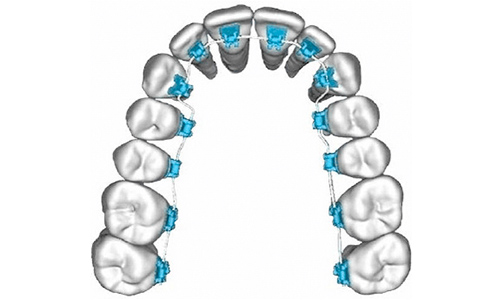

裏側矯正(リンガル矯正)

「表から見えない」のが人気の裏側矯正、

当院では3Dデジタル矯正でさらに多くのメリットをもたらしています。

一般的なようで実は技術力を必要とされる裏側矯正は3Dデジタル矯正でそのデメリットが解消されています。

3Dデジタル矯正が治療の効率化を実現

表側矯正よりも矯正歯科医の技術レベルを必要とされ、治療の段階も少し複雑なので治療期間は長期になりやすかった裏側矯正ですが、3Dデジタル矯正の導入により

抜歯する場合は〜1年半

非抜歯では〜1年

従来の裏側矯正よりも非常に効率的な治療が可能になりました。